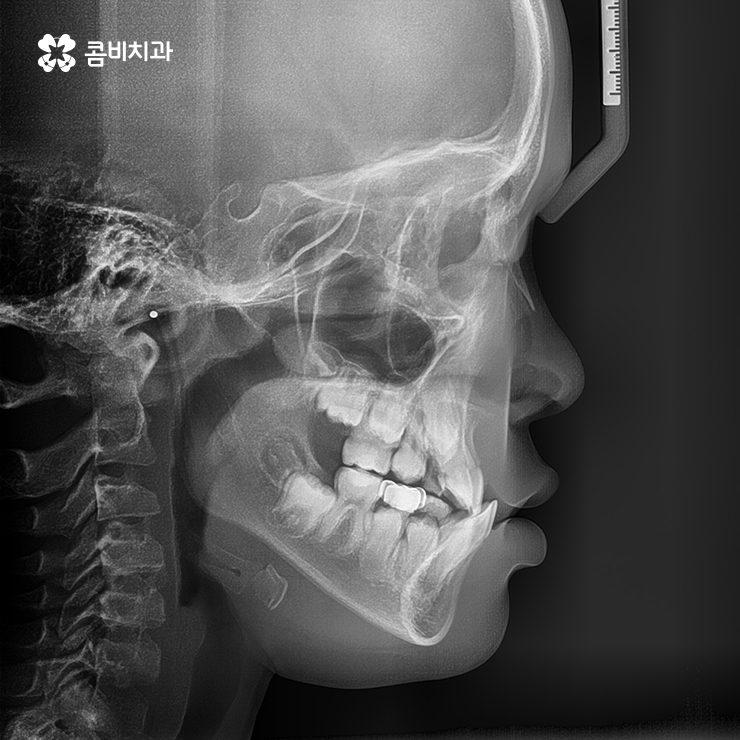

(위턱과 아래턱의 성장 불균형으로 인해 주걱턱이 발생한 사례)

위와 같은 사례를 부정교합 중에서도 반대교합이라고 하는데

성장기에 턱이 성장을 할 때 아래턱이 과도하게 발달을 하거나

반대로 위턱의 성장이 부족한 경우에 이와 같은 주걱턱 증상이 발생할 수 있습니다.

구강검진을 통해서 이러한 골격 부조화를 조기에 발견하여

치료를 시작할 경우 아래턱은 성장을 억제시키고

위턱은 성장을 유도하는 TTBA라고 하는 성장기 교정 장치를

활용하여 주걱턱의 교정이 비수술적인 방법으로 가능합니다.